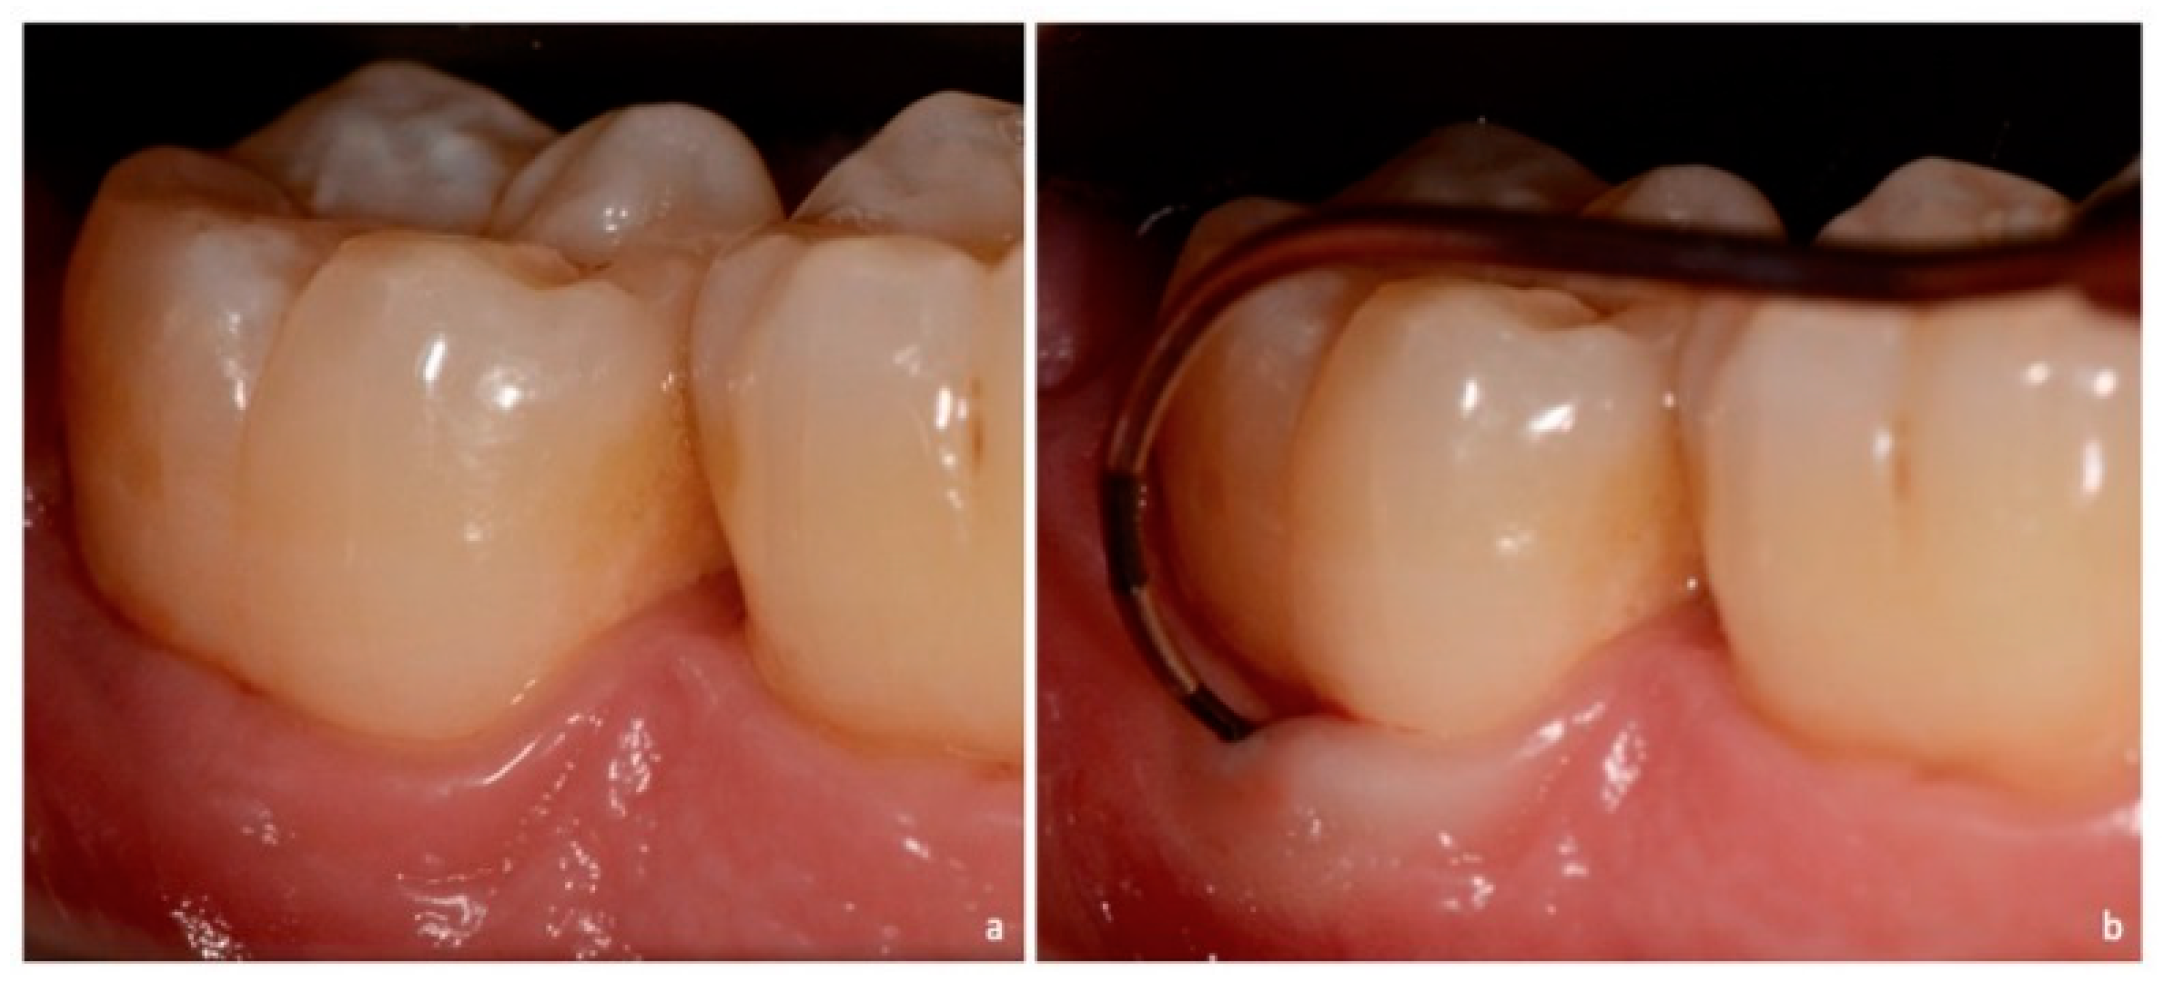

Marking Guidelines

| NEI | The furcation lesion is not clinically exposed. The horizontal attachment loss is 2 mm or less. |

| NEII | The furcation lesion is not clinically exposed. The horizontal attachment loss is 3 mm or more. |

| NEIII | The furcation lesion is not clinically exposed. The horizontal attachment loss is total, with through and through opening of the furcation. |

| EI | The furcation lesion is clinically exposed. The horizontal attachment loss is 2 mm or less. |

| EII | The furcation lesion is clinically exposed. The horizontal attachment loss is 3 mm or more. |

| EIII | The furcation lesion is clinically exposed. The horizontal attachment loss is total, with through and through opening of the furcation. |